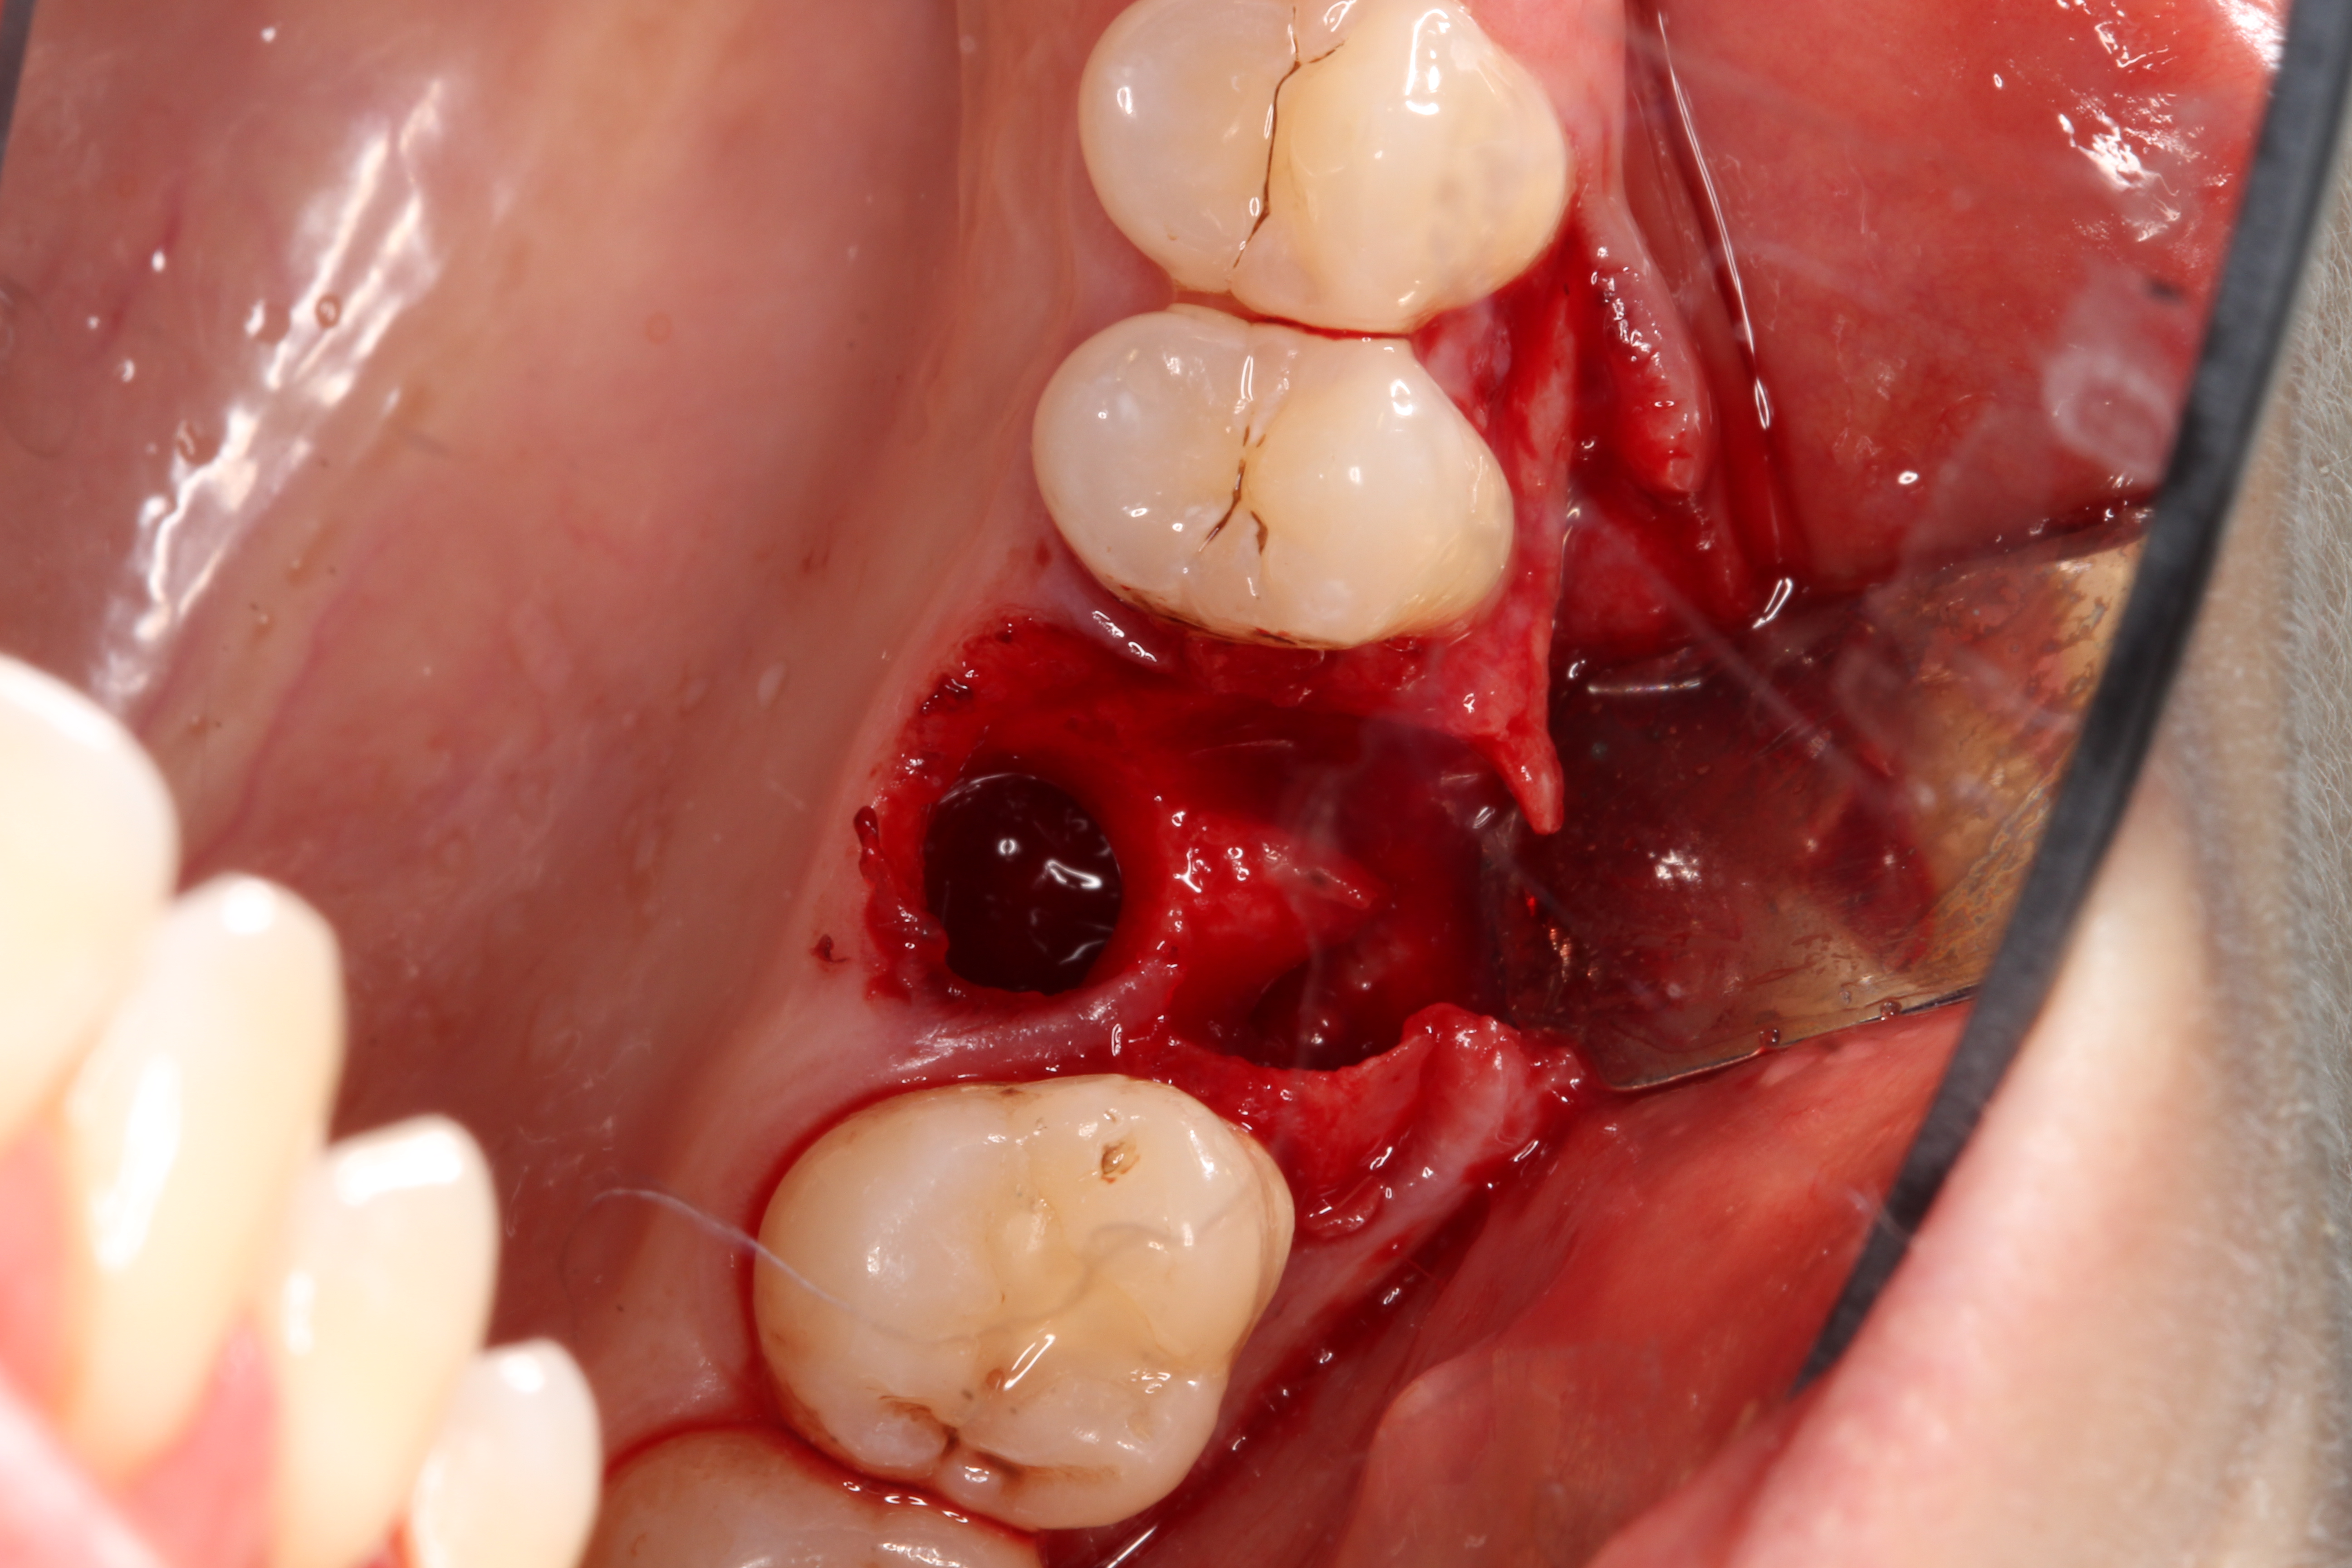

1. Minimally invasive, atraumatic extraction of the remaining tooth structure with the use of periotomes or similar instruments as well as sectioning of the tooth, when indicated, should be performed to minimize any unnecessary trauma to the thin cortical bone and surrounding soft tissues (Figure 4).

Fig 4. Atraumatic extraction of the hopeless tooth.

Figure 4